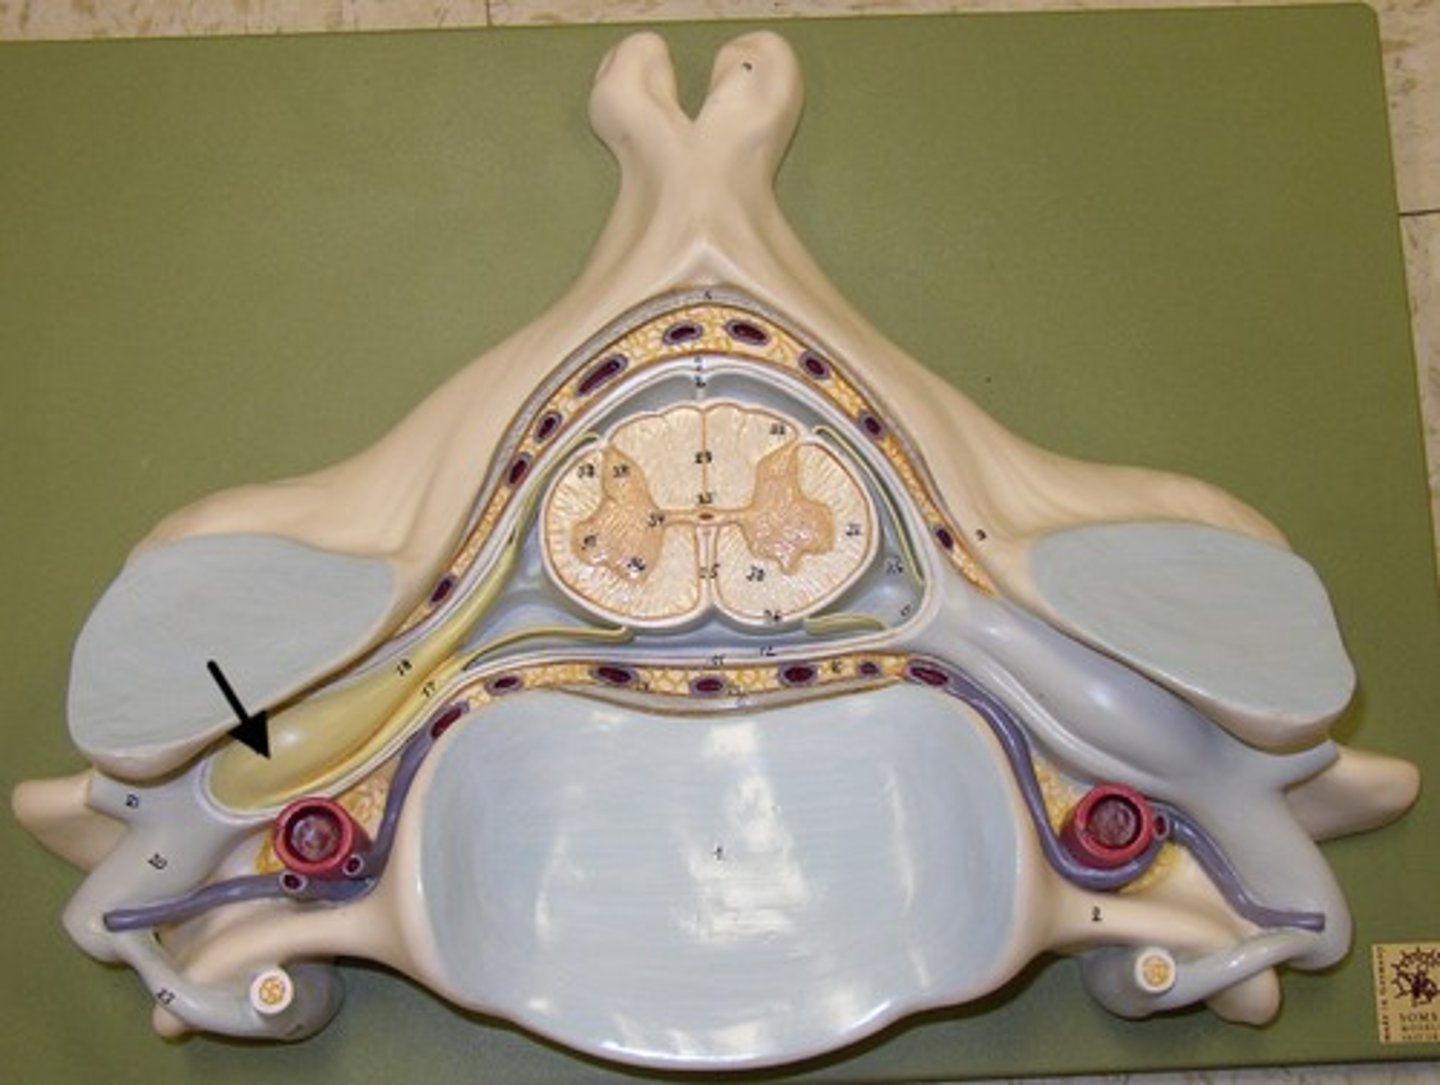

epidural space

dura mater

thick, outermost layer of the meninges surrounding and protecting the brain and spinal cord

subdural space

space between dura mater and arachnoid mater

arachnoid mater

middle layer of the meninges

B on model

subarachnoid space

a space in the meninges beneath the arachnoid membrane and above the pia mater that contains the cerebrospinal fluid

pia mater

the delicate innermost membrane enveloping the brain and spinal cord.

denticulate ligaments

extensions of pia mater that secure cord to dura mater laterally

posterior root

axons of sensory neurons

posterior root ganglion

anterior root

axons of motor neurons

spinal nerve